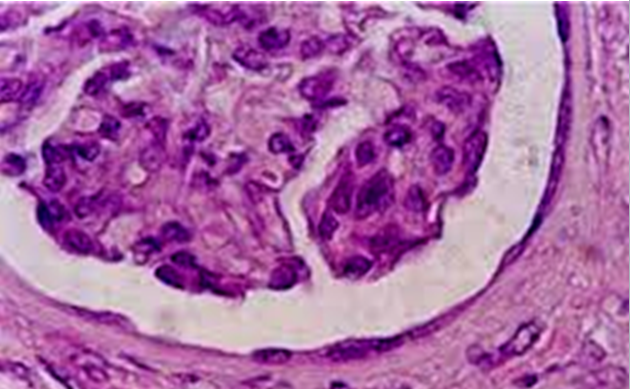

LM picture of transitional epithelium